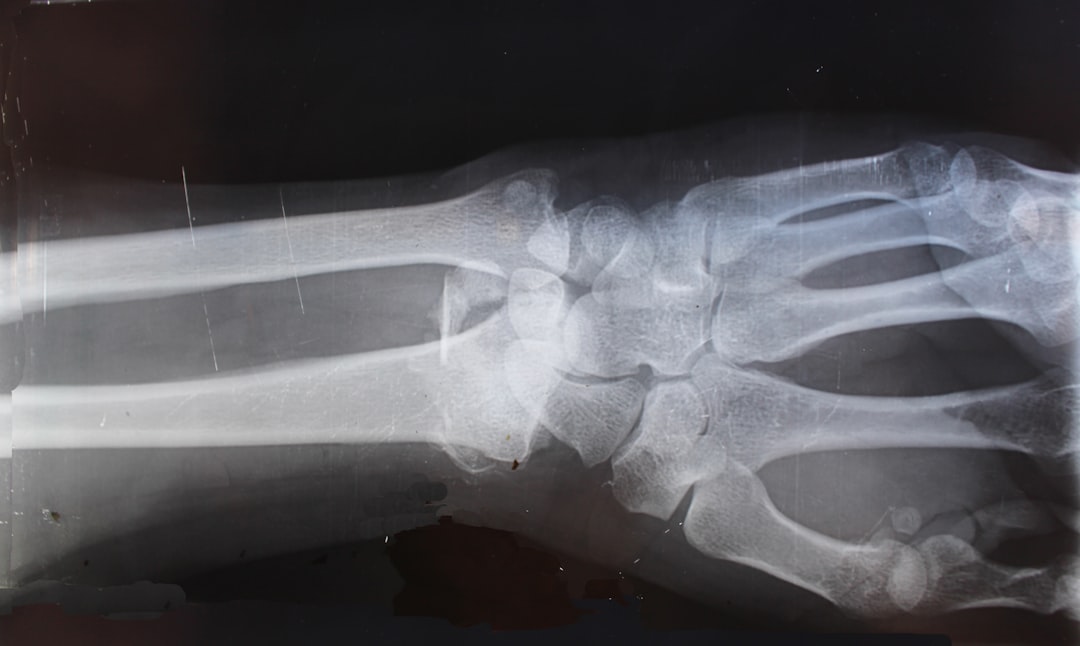

정형외과 중요성

정형외과는 뼈, 관절, 인대 및 근육과 관련된 질환을 치료하는 전문 분야입니다. 모든 연령대에 걸쳐 다양한 문제가 발생할 수 있으며, 이로 인해 일상생활에 큰 불편을 초래할 수 있습니다. 따라서 정형외과 전문의와의 상담은 필수적입니다. 문제를 무시하거나 미루다 보면 상황이 더 심각해질 수 있으니, 적절한 시기에 진료받는 것이 중요합니다. 일요일 정형외과 토요일 진료 시간도 이 점에서 크게 기여할 수 있습니다. 어떤 시간을 선택하든, 전문가의 도움을 받는 것이 성공적인 치료로 가는 첫걸음이죠. 그럼, 이 중요한 진료 시간이 어떻게 운영되는지 살펴볼게요!